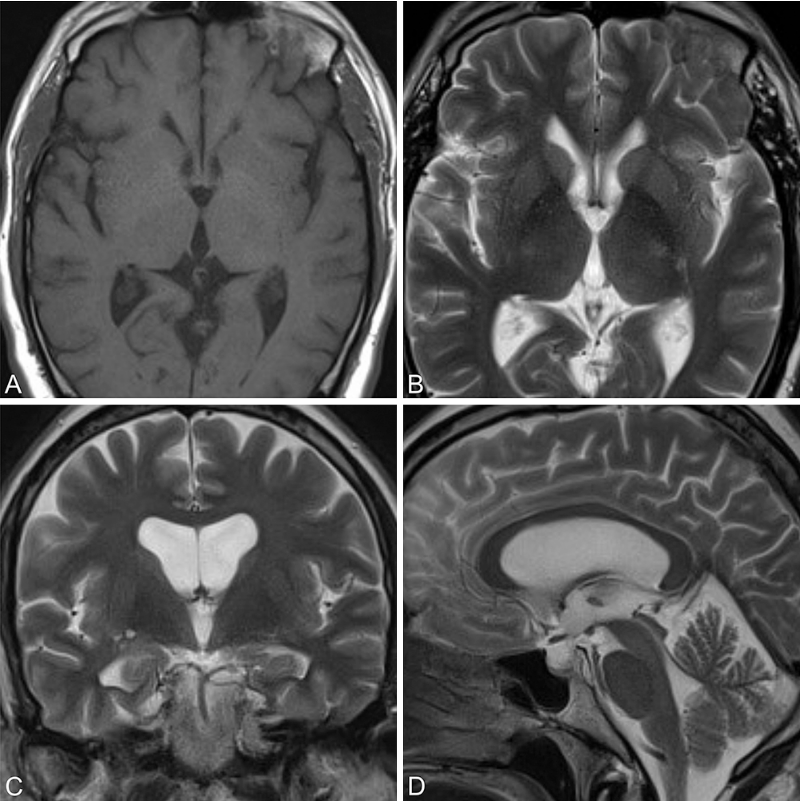

狭窄脑室内的内镜肿瘤切除术。 (a) 冠状位T2加权磁共振图像显示侧脑室内肿瘤,脑室空间狭小。 (b) 将内镜向鞘管内回缩,以创造额外工作空间。 (c) 使用鞘管将肿瘤从尾状核牵开,以便显露肿瘤基底并用双极电凝处理。缩写:B,双极电凝电极;CN,尾状核;S,内镜鞘;T,肿瘤。

当脑室因各种原因处于狭窄状态时,神经内镜的操作空间极为有限,器械活动度严重受限,手术难度随之大幅上升。内镜鞘在这一困境中展现出独特价值:将鞘管置入脑室后,把脑室镜在鞘管内适度向后回缩,即可在鞘管远端前方营造出额外的操作空间,让外科医生能够以更大的器械运动角度和更宽的操作范围完成复杂的脑室内解剖与病灶处理。